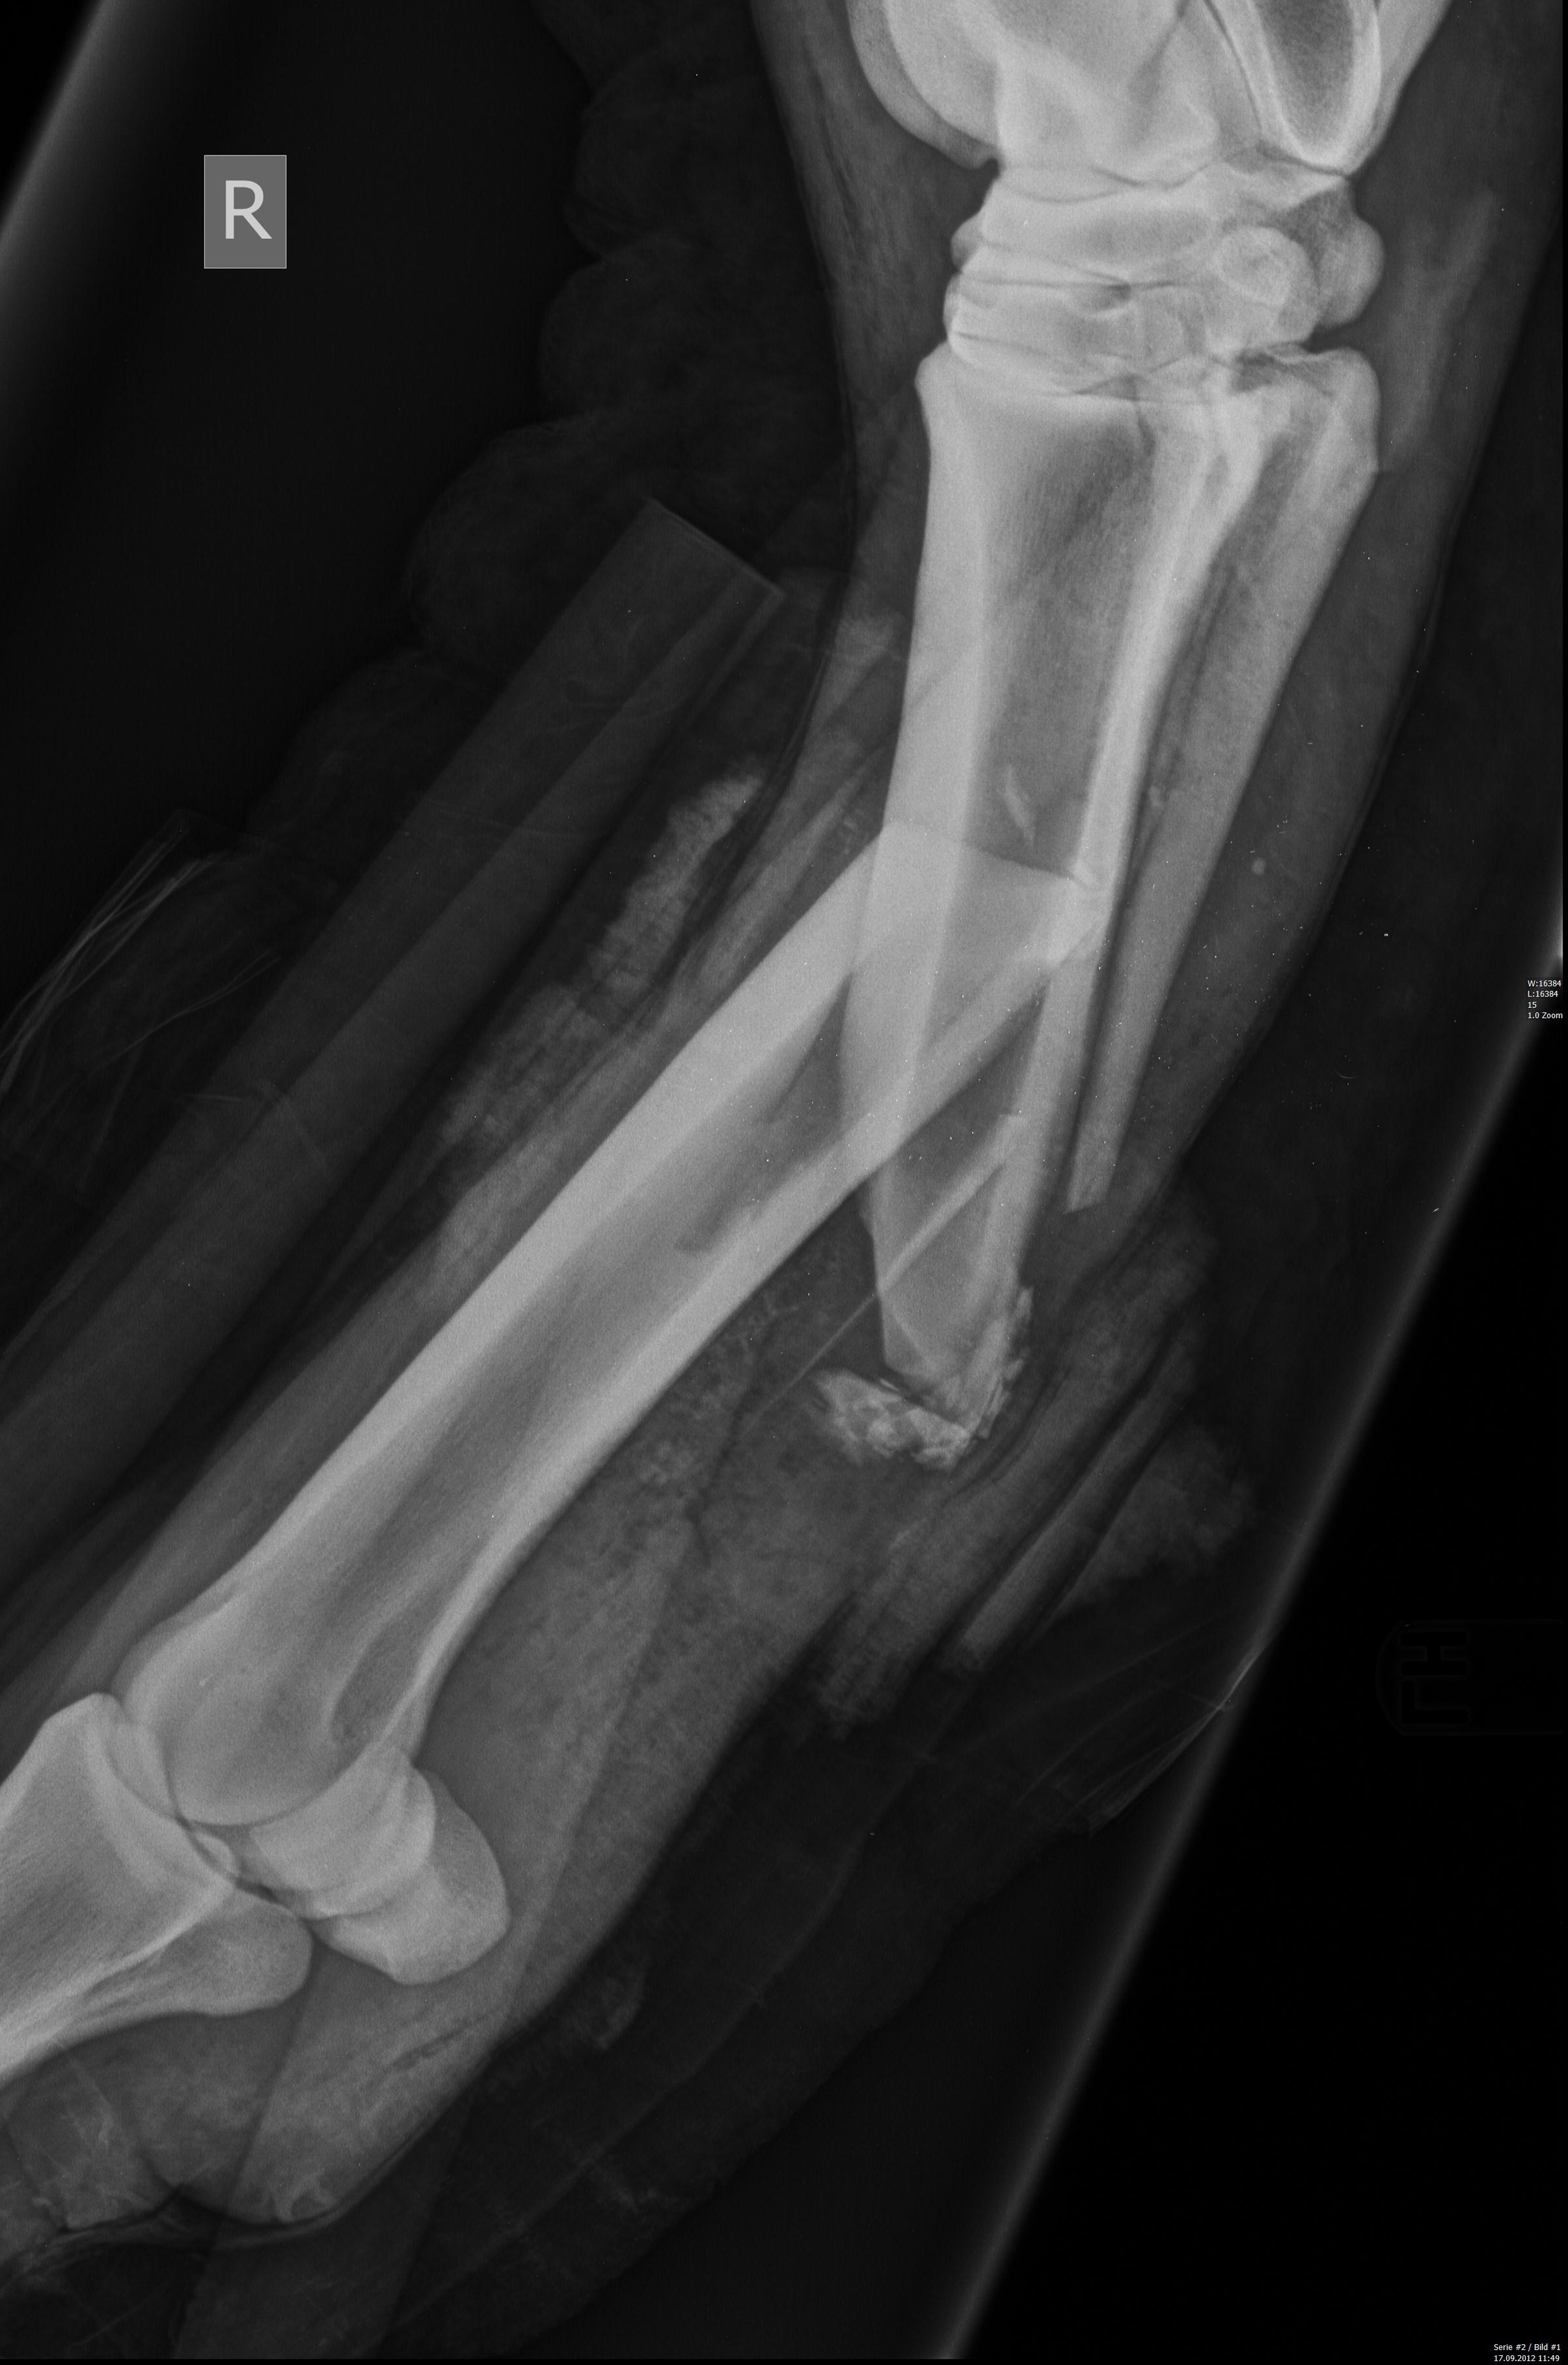

Röhrbeinfraktur